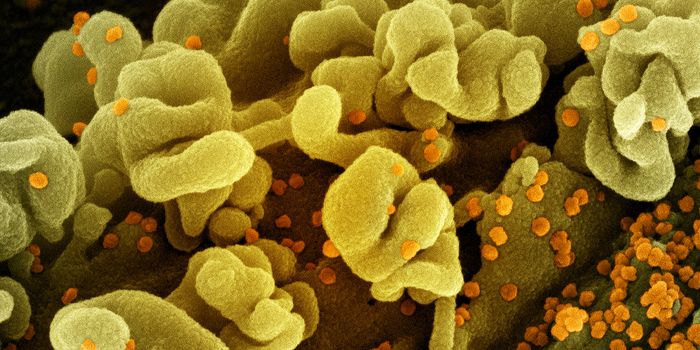

APR 07, 2023MicrobiologyScientists are still learning about SARS-CoV-2, and the illness it causes, COVID-19. While we know a lot about how the v ...